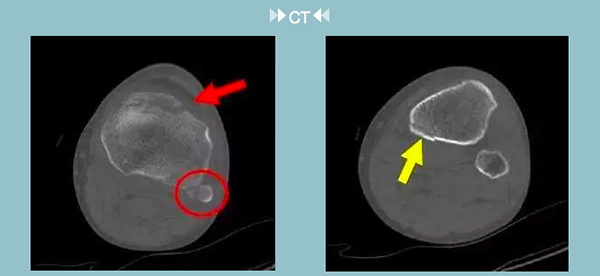

真是一做吓一跳!不仅对于平片上圆圈内已确诊的腓骨上端撕脱骨折,在CT影像中也能清晰看见,对于刚刚深深隐藏在平片中的“小病魔”——可疑透亮线影,被暴露无遗地展现在CT影像中。

通过二维重建图像,我们确诊患者为胫骨平台多发骨折(不同颜色箭头指向各个骨折部位)。看完CT报告之后,我们可以确诊:王伯伯左侧腓骨上端撕脱骨折、胫骨平台多发骨折。